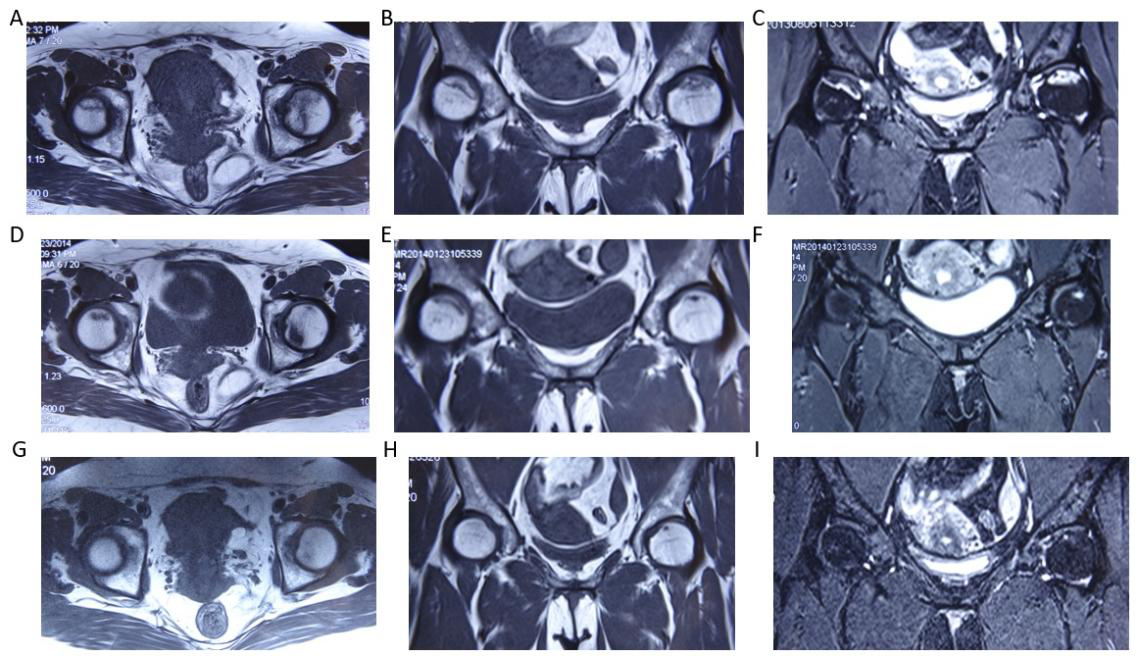

病例,女性49岁,病程3年。A- C:MRI显示双侧股骨头轻度塌陷,双线征,软骨信号消失。D- F:治疗6个月后,明显改善。G-I:治疗1年后,MRI信号正常,恢复正常工作。

A case of stage 3 femoral head necrosis treated with MRI repair changes, female, 49 years old, with a course of 3 years. A - C: MRI shows mild collapse of bilateral femoral heads, double line sign, and disappearance of cartilage signal. D-F: After 6 months of treatment, there was a significant improvement. G-I: After one year of treatment, the MRI signal was normal and normal operation resumed.